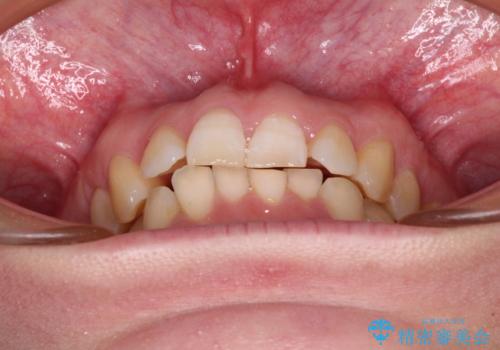

インビザライン単体で対応ることも検討できますが、達成する可能性が低いため、カリエールディスタライザーという補助装置を併用して、より確実性を上げることとしました。

奥歯の咬み合わせと深い咬み合わせを改善した後、インビザラインで歯列を整えることとしました。